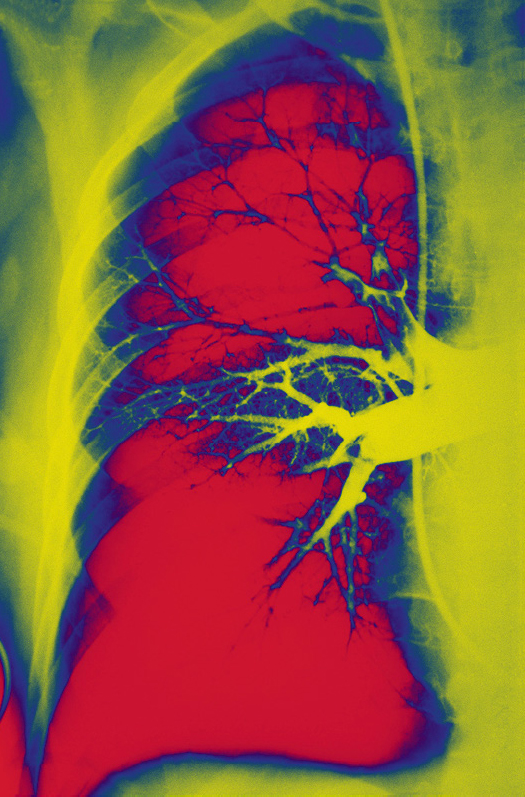

Diagnostische vertraging bij longembolie

Op afdelingen Spoedeisende Hulp wordt de diagnose ‘longembolie’ regelmatig later dan gewenst vastgesteld of zelfs helemaal gemist. Hoe vaak deze diagnostische vertraging zich voordoet in de huisartsenpraktijk is slecht bekend.